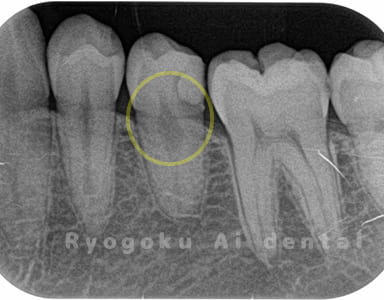

Case03

違和感があるとのことでレントゲン撮影を行なったところ、プラスチックの被せ物の中で虫歯が広がっていると判断。レントゲンの状態からも神経にかなり近いため、患者様と相談し、断髄治療を行なったケースです。3年間のフォローアップ期間中で現在トラブルはなし。

<リスク・副作用>

術後は痛み、腫れ、痺れなどの副作用が生じる場合があります。症状が再発する可能性があります。その場合は抜髄する必要があります。